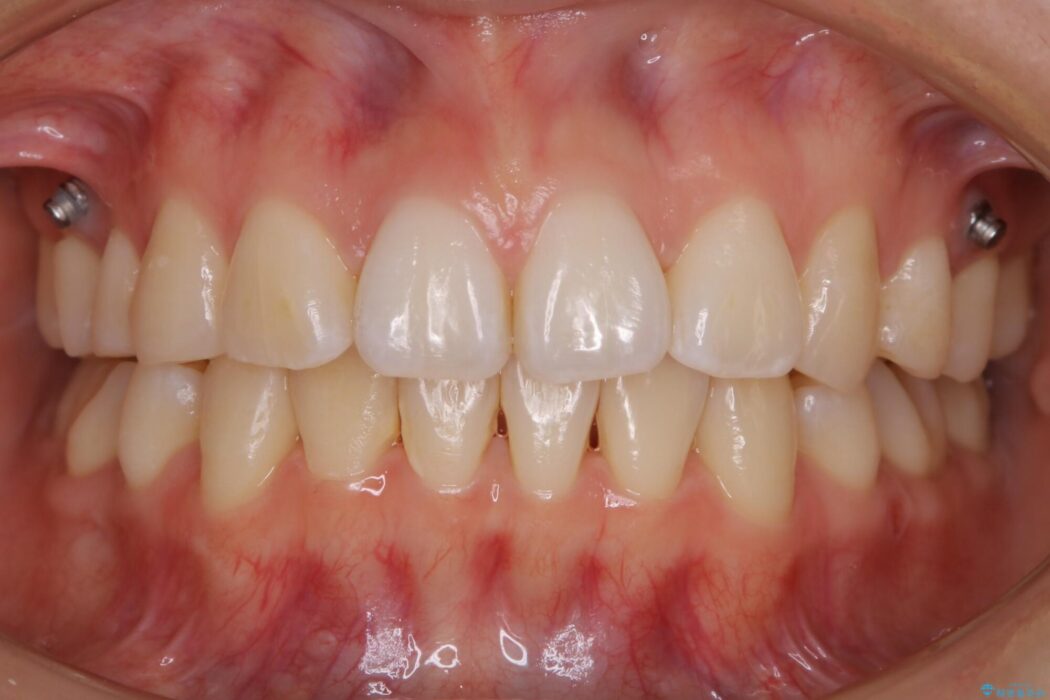

治療後について

後戻りしていた歯列もきれいに整い患者様にはご満足いただけました。

小学生~高校生の間に矯正治療をされている方で、その後の成長や生活の変化におけるリテーナー(後戻り防止装置)の継続使用が困難となり、叢生(ガタつき)が時間の経過で再発してしまうケースが多くあります。

一度目の矯正治療の際に抜歯をしていたり後戻りでのガタつきの度合いによって再矯正における治療期間が最初の矯正治療と同程度に要する場合もあります。